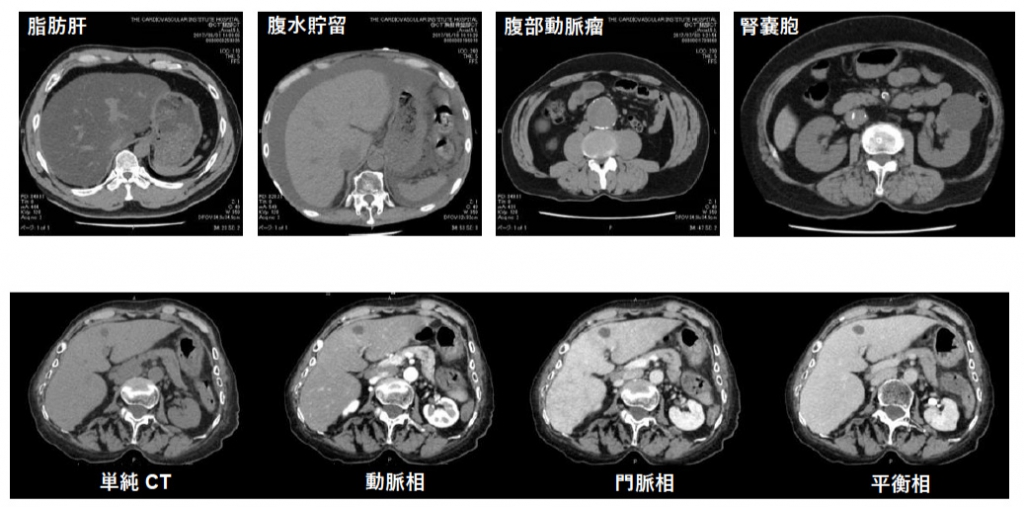

腹部・骨盤CT

腹腔内臓器の病変や悪性腫瘍、血管病変などを診断します。

特にガスや脂肪によりレントゲンやエコーでは見えづらい深部臓器の描出が可能です。

急性腹症の原因や腫瘍性病変の精査など検査内容により造影剤を使用します。

腹部単純CTは5分程度の検査となります。

胸腹骨盤CTA

造影剤を使用し任意の時相で撮影することで、単純CTではわかりづらい各臓器の血流状態や血管の詳しい情報を得ることができます。

動脈瘤・動脈解離の評価や人工血管置換術・ステントグラフト留置術などの術後評価に有用です。

大血管が造影剤で濃く満たされている時相(動脈相)で撮影することにより血管を3D表示し立体的に観察することもできます。